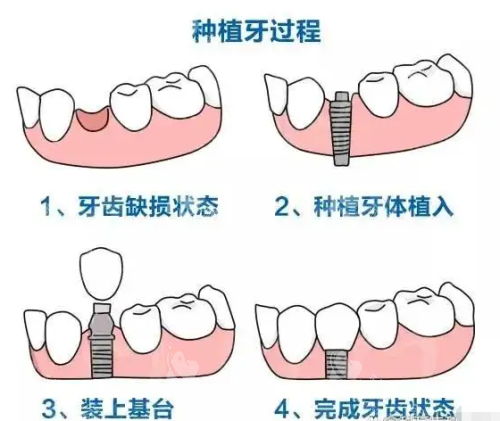

种植牙流程

种植牙的整个过程犹如建造一座坚固的房屋,需历经多个步骤。

接着是植入种植体,恰似用钢筋水泥浇筑地基。在局麻或静脉麻醉下,医生将钛合金种植体比较准植入牙槽骨,如同 “埋入地基钢筋”。部分机构会采用 AI 动态导航技术,避开神经血管,误差小于 0.1 毫米。若骨条件良好,拔牙后可立即植入种植体,缩短治疗周期。植入后,医生会对仅 3 - 5 毫米的切口进行缝合,术后 1 - 2 周拆线。

然后是骨结合阶段,如同水泥静置养护。种植体与牙槽骨需 3 - 6 个月完成 “骨结合”,形成稳固的人工牙根。在此期间,前牙区可安装临时义齿,不影响美观和进食。不过,吸烟、糖尿病等因素可能会延长愈合时间,患者需严格遵医嘱。

之后是安装基台,好比搭建房屋主体结构。骨结合完成后,医生会切开牙龈暴露种植体,安装愈合基台,1 - 2 周后牙龈形态改善自然,为牙冠提供理想 “底座”。

然后是佩戴牙冠,如同房屋的精装修。医生会通过智能化扫描或传统取模,制作个性化牙冠,材质可选全瓷或烤瓷。全瓷冠通透逼真,适合前牙;烤瓷冠耐磨经济,适合后牙。安装牙冠时,医生会调整咬合高度、邻接关系,确保患者咀嚼舒适。